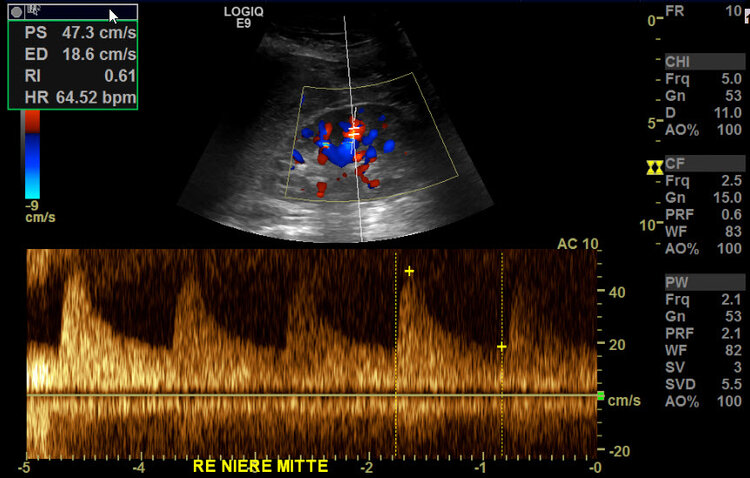

Bei der Nierenarterienstenose werden die Nieren nicht mit genügend Blut versorgt, um ihre Funktionen auszuführen. Dies kann zu Bluthochdruck, Nierenversagen und anderen schwerwiegenden Komplikationen führen. Risikofaktoren für eine Nierenarterienstenose sind u.a. Rauchen, Bluthochdruck, Diabetes und hohes Alter. Selten kommt es in jungen Jahren zu einer lokalen Gefässwandverdickung (fibromuskuläre Dysplasie = FMD) deren Ursache noch unbekannt ist. Das Beschwerdebild ist der atherosklerotisch bedingten Nierenarterien-Verengung vergleichbar.

Die Diagnose von Durchblutungsstörungen in den inneren Organen erfolgt in der Regel durch bildgebende Verfahren wie Ultraschall, Angiographie oder CT-Scans.